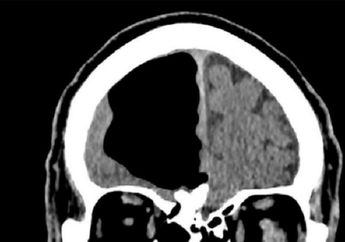

Merasa Badannya Kurang Sehat, Seorang Kakek Malah Menemukan Sebagian Otak Kanannya 'Hilang'!

7 Tahun yang lalu - Kakek ini awalnya merasa kurang sehat. Tapi setelah diperiksa dokter, ia malah menemukan sebagian otak kanannya 'hilang'. Penyakit inilah yang diderita kakek itu.